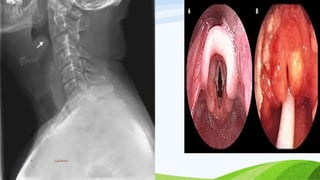

EPIGLOTTITIS

• H.Influenzae type B – MC cause

• Starts with a minor URTI that progresses

rapidly within few hours

• High grade fever & dysphagia

• Tripod position , toxic appearing & drooling

• Frequent cough is absent

Lakshmi8

Lakshmi9